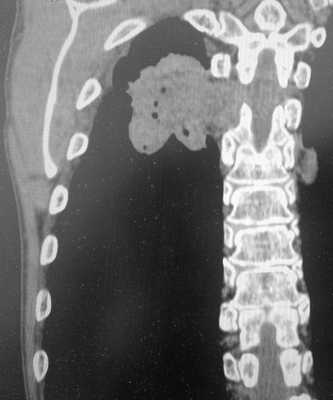

Пример контактного распространения опухоли: мезотелиома плевры, прорастающая в верхнюю легочную долю и грудную стенку. Спиральная компьютерная томография (МСКТ).

Контактные метастазы представлены мягкотканным объемным образованием, прорастающим из сопредельного органа. Это может быть пищевод, трахея, гортань, реже опухоль исходит из плевры (мезотелиома), диафрагмы, ребер, позвонков.